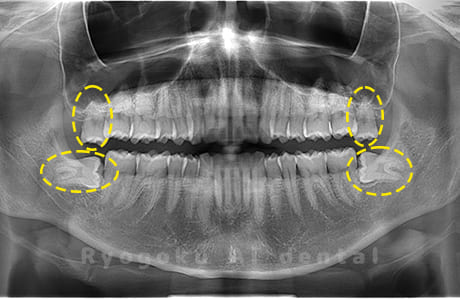

Case03

-

- 原因

- 上顎、下顎の親知らず

- 治療内容

- 上下4本の親知らずを抜歯したケースです。

<リスク・副作用>

手術後は痛み、腫れ、痺れなどの副作用が生じる場合があります。